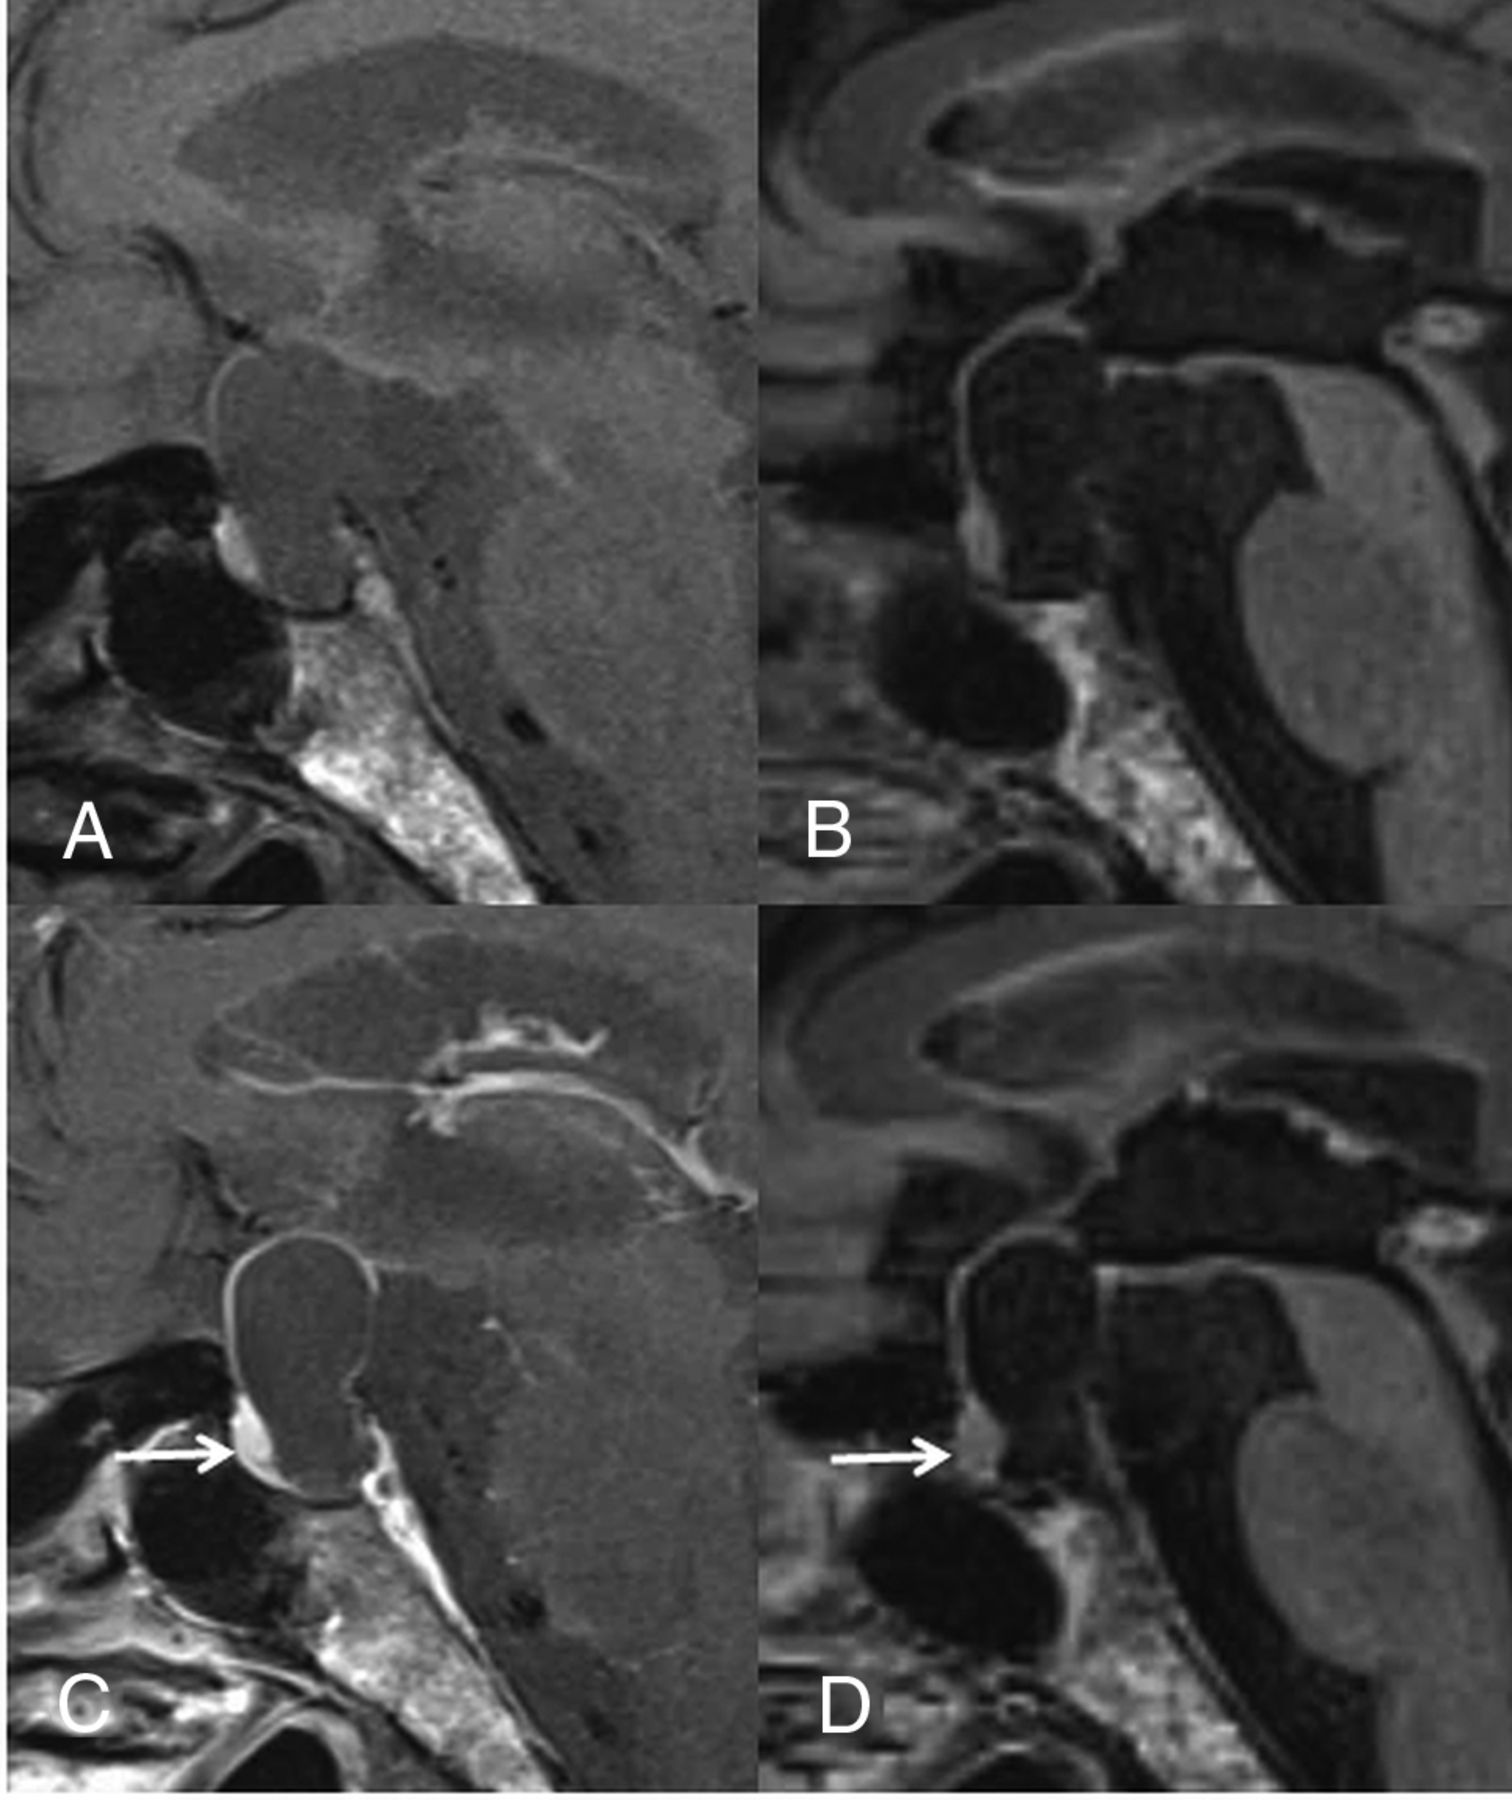

A 40-year-old woman with an RCC. On the postcontrast T1WI (C) compared with the precontrast T1WI (A), the cyst wall is enhanced (grade 2), as is the pituitary gland. Unlike the precontrast 3D T2-FLAIR image (B), the postcontrast image (D) shows no contrast enhancement (grade 0). Different from the postcontrast T1WI (C), the pituitary gland is not enhanced on the postcontrast 3D T2-FLAIR image (arrow in D). The observer judged this lesion as equivocal (scale 3) at the conventional MR interpretation, whereas the confidence level was changed to probably an RCC (scale 2) by the addition of 3D T2-FLAIR interpretation.

A 60-year-old man with RCC. On the postcontrast T1WI (C) compared with the precontrast T1WI (A), the cyst wall is enhanced (grade 2) and a solid enhanced area is seen (arrow). Unlike the precontrast 3D T2-FLAIR image (B), the postcontrast image (D) shows no contrast enhancement of the wall (grade 0) and the solid area (arrow). The observer judged this lesion as probably a CCP (scale 4) at the conventional MR interpretation, whereas the confidence level was changed to probably an RCC (scale 2) by the addition of 3D T2-FLAIR interpretation.